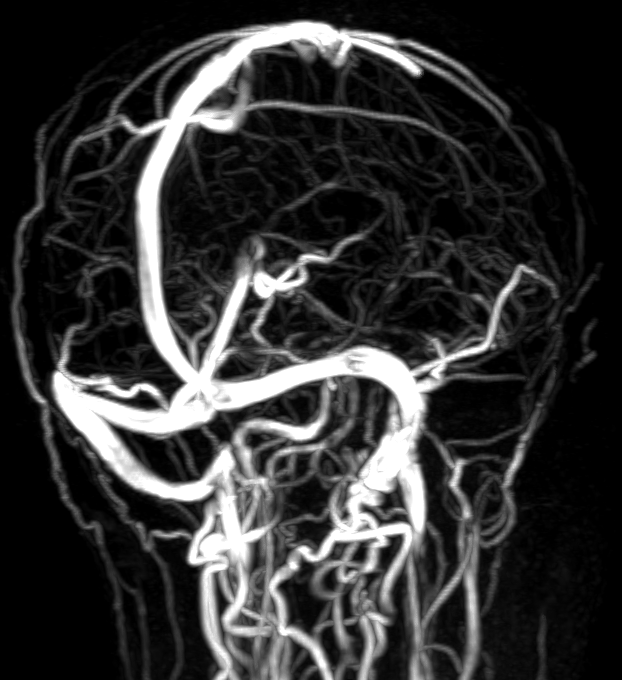

Показания для проведения МР бесконтрастной ангиографии артерий и вен головного мозга:

- головные боли;

- головокружения;

- потеря сознания;

- нарушения поведения;

- потеря чувствительности и слабость в конечностях;

- сонливость и спутанность сознания, сопровождающие головную боль.

Как проводится МР бесконтрастная ангиография артерий и вен головного мозга?

Перед укладкой в томограф необходимо снять все металлические предметы. После этого пациент ложится на стол сканера, который постепенно перемещается в аппарат. Во время сканирования следует лежать неподвижно, чтобы получаемые изображения были четкими и неискаженными.